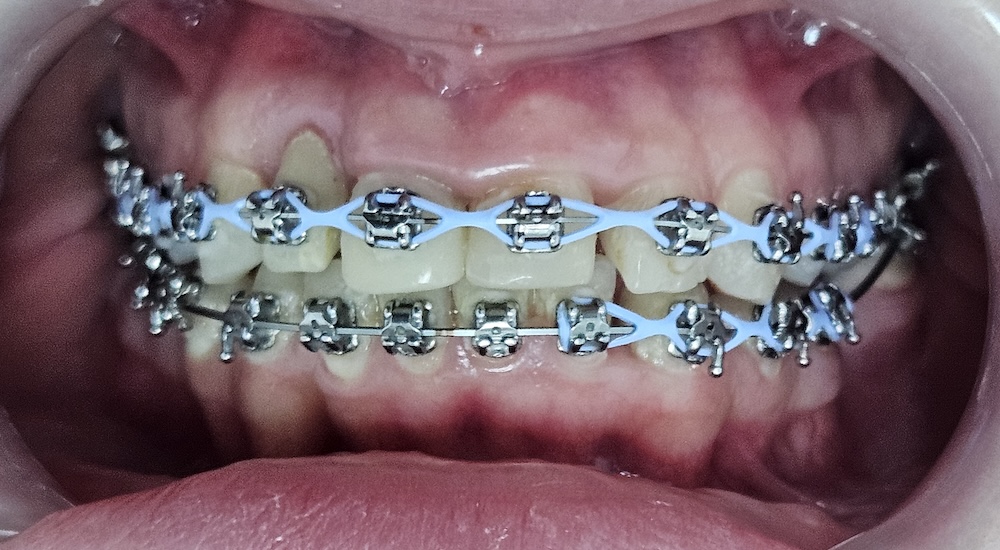

Вирівнювання зубів

Перед встановленням брекет-системи були видалені зуби мудрості. Це робиться не “про всяк випадок”, а для того, щоб звільнити місце і дати можливість зубам зайняти правильне положення без тиску ззаду. У цьому клінічному випадку перед брекетами видалили зуби мудрості, щоб створити місце для переміщення зубів і зменшити ризики ускладнень. Потребу в такому видаленні визначають індивідуально. В кінці 2023 року зафіксували металеву самолігуючу брекет-систему. Самолігуюча означає, що дуга фіксується без додаткових гумок — це дозволяє зменшити тертя і більш контрольовано переміщати зуби.